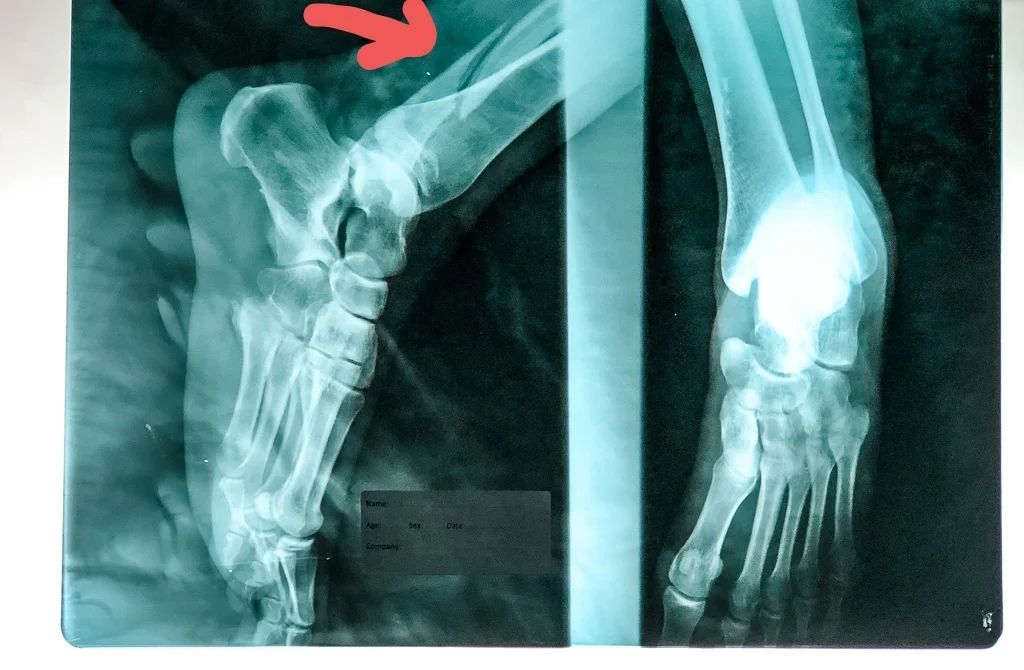

There it was staring back at me... A complete break in my fibula bone right above my ankle. F**K!

IMG_9285-3.jpg